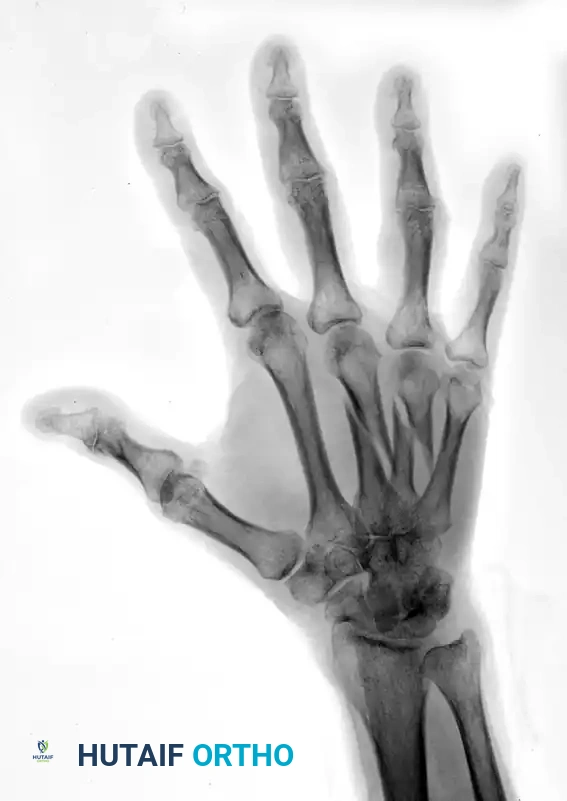

Preoperative Imaging:

FIGURE 67-42 A: Preoperative AP radiograph showing shortened and oblique middle and ring metacarpal fractures.

FIGURE 67-42 B: Preoperative oblique radiograph demonstrating the fracture geometry, which is highly suitable for interfragmentary fixation.

Postoperative Imaging:

The fractures were reduced anatomically. Lag screws were placed to provide interfragmentary compression. To neutralize the sagittal bending moment—particularly in the ring metacarpal—a supplemental 24-gauge cerclage wire was applied.

FIGURE 67-42 C: Postoperative AP radiograph showing anatomic reduction and rigid fixation.

FIGURE 67-42 D: Postoperative oblique radiograph. Note that the sagittal bending moment of the ring metacarpal shaft fracture was successfully offset by the supplemental 24-gauge cerclage wire fixation.